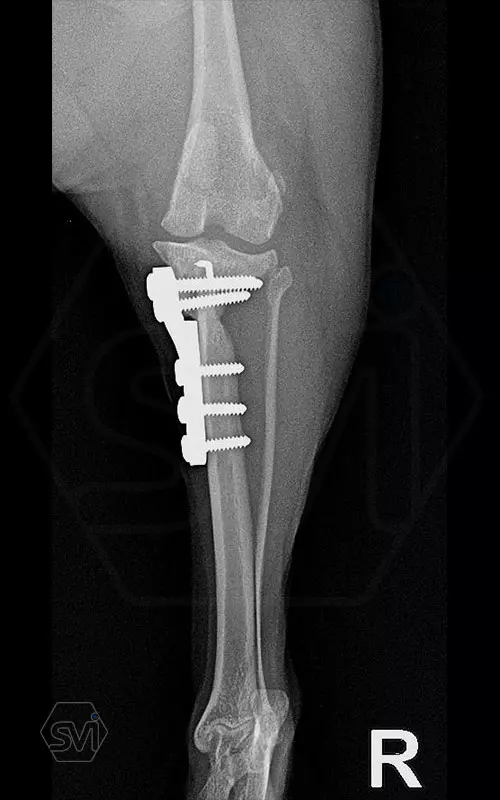

Introducing the TPLO-M „terraced” plate family from Smartvetimplants.com

In small dogs, medial patella luxation (MPL) and the rupture of anterior cruciate ligament (RACL) often occur simultaneously. During the surgical procedure, the joint must be stabilized and the patella fixed in the middle axis at the same time.

The solution of Smatvetimplants is the TPLO-M plate family with terrace:

Mini TPLO-M plate:

non-locking, symmetrical, with 2.2 mm terrace (degree of shift), for standard 2.0 mm AO cortical screws (1.5 and 2.4 mm screws can also be inserted), material steel. Optimized for R12 blades.

Between October 2020 and December 2021, we performed 19 TPLO-M surgeries at the Animal Hospital in Nyíregyháza,: 16 times used the mini (2.0 R12) and 3 times the small (2,4 R15) TPLO-M plate.

The experience is very encouraging, we find the system and plates suitable for the simultaneous treatment of MPL and RACL. ( in case of 4/4 pat. lux. also). We will back soon with details.